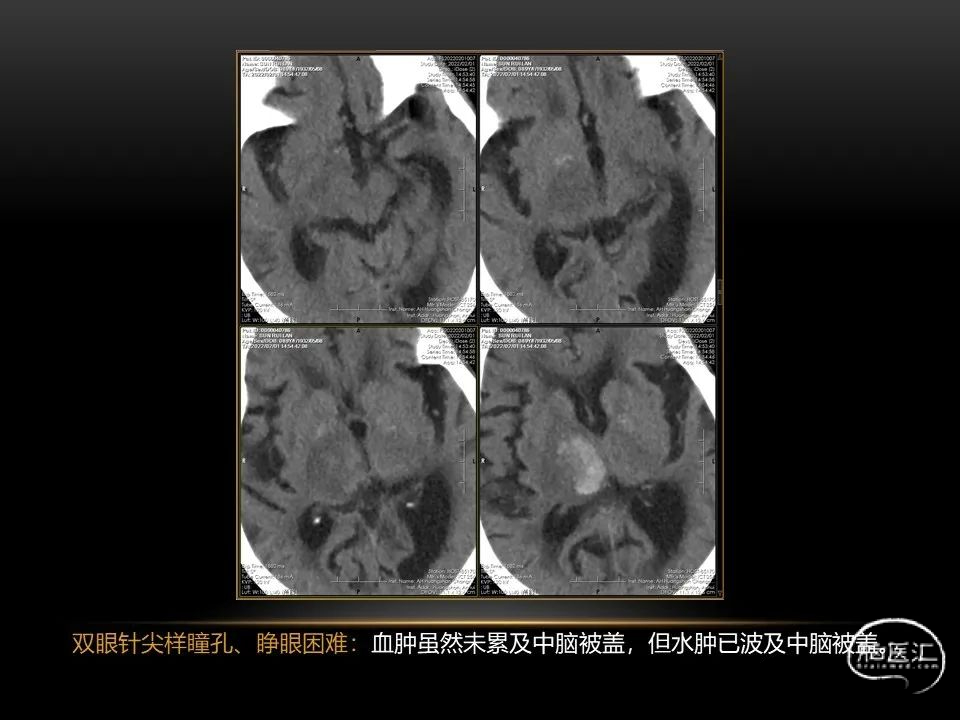

自发性脑出血临床上很常见,不同原因有特征性的出血部位。例如:基底节出血和丘脑出血大多是高血压性脑出血;脑叶出血,特别是多次复发的脑叶出血多见于老年人的脑血管淀粉样变。

自发性脑出血不仅仅累及内囊后肢才会出现偏瘫及偏身感觉障碍,病变累及大脑脚或辐射冠同样有可能有类似症状和体征。内囊、辐射冠、大脑脚等结构之间是延续的,只是不同区域不同名称而已。定位诊断需要对解剖结构概念清晰,读片准确辨认,灵活掌握。